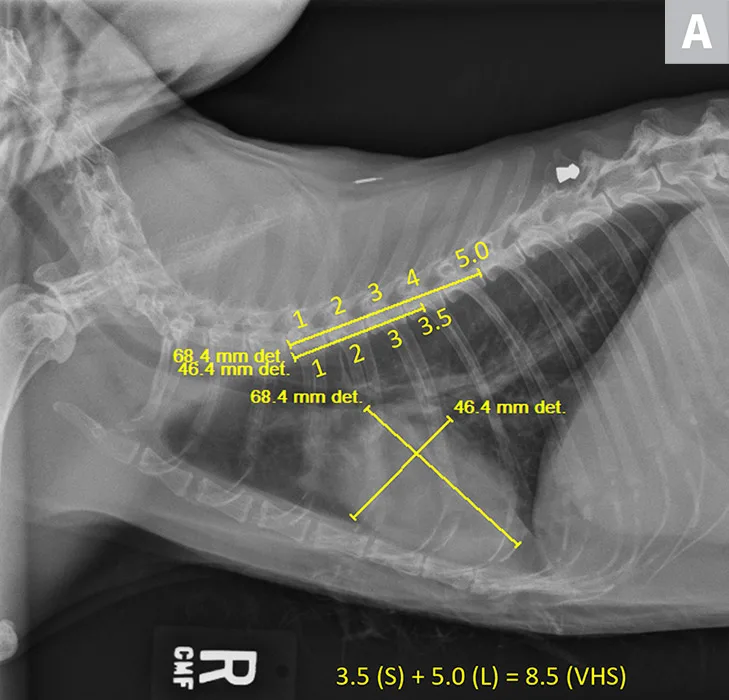

VHS calculation in a clinically normal cat using a left lateral radiograph (A). L (ie, long axis; 4.4) is drawn from the carina to the most ventral aspect of the apex. S (ie, short axis; 3.3) is drawn perpendicular to L at the widest aspect of the heart, extending to the cranial and caudal borders. S and L are transposed along the spine from the cranial aspect of T4 using calipers. The number of vertebrae traversed (rounded to the nearest tenth) are summed to calculate VHS (7.7). Orthogonal radiograph of the patient is also shown for more complete evaluation of cardiac silhouette (B).

VHS calculation in a cat diagnosed with HCM using a right lateral radiograph (A). L (ie, long axis; 5.0) is drawn from the carina to the most ventral aspect of the apex. S (ie, short axis; 3.5) is drawn perpendicular to L at the widest aspect of the heart, extending to the cranial and caudal borders. S and L are transposed along the spine from the cranial aspect of T4 using calipers. The number of vertebrae traversed (rounded to the nearest tenth) are summed to calculate VHS (8.5). Pulmonary vasculature is prominent but within normal limits, and there is a ballistic metallic foreign body (likely a bullet) in the dorsal subcutaneous tissue of the caudal thorax. Moderate spondylosis deformans exists at T13-L1 and L1-L2, and there is bridging spondylosis deformans at T10-T11. Intervertebral disk space at T10-T11 is collapsed, and there is fusion at the 2 vertebral bodies. Orthogonal radiograph of the patient is also shown for more complete evaluation of cardiac silhouette (B).